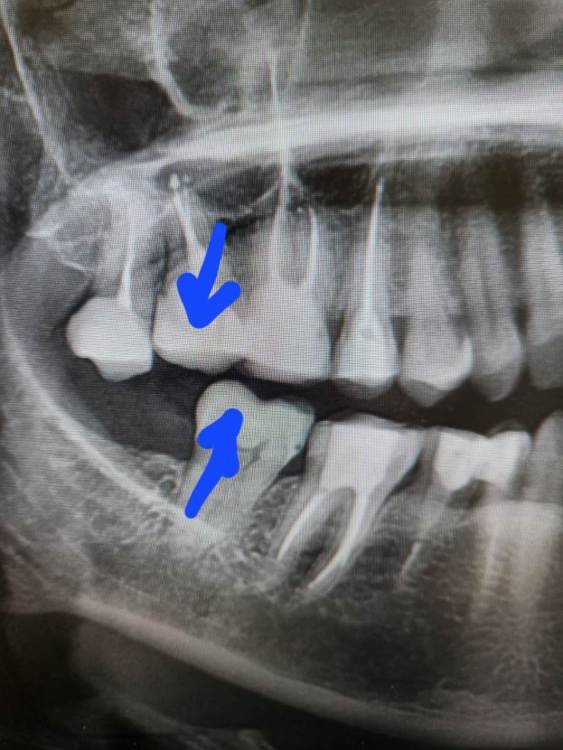

Ольгаxxx Опубликовано 17 февраля, 2023 Поделиться Опубликовано 17 февраля, 2023 Здравствуйте. Уважаемые врачи, столкнулась с проблемой, что когда-то пролеченный 7 зуб стал разрушаться и вызвал резорбцию кости. К слову, зуб не участвует в прикусе, так как стоит ближе к щеке. Зуб еще не удален. Панорамный снимок прилагаю. Будьте любезны, подскажите, как правильно поступить, удалить верхнюю 7и 8 поставить имплантат? Получится ли одномоментно это сделать? Ширина кости оставшейся 6 мм. А второй вариант не ставить имплантат, так как он все равно не будет нагружаться, внизу нет антагониста. Либо поставить сначала вниз имплантат, а затем со временем вверх? Но опять таки это 8зуб по сути, нужен ли имплантат там? Посоветуйте, как быть в моем случае. Благодарю. Ссылка на комментарий

Irouil Опубликовано 17 февраля, 2023 Поделиться Опубликовано 17 февраля, 2023 Внизу есть 7-й зуб, почему запротезированный верхний 7-й не должен быть в прикусе? Возможно, Вам нужна консультация ортодонта, ибо это может быть показателем выраженной скученности нижнего зубного ряда или его смещения. По этим данным не сказать - можно или нет установить имплант одномоментно с удалением, но с очень большой долей вероятности - возможно (ибо возможно почти всегда). Нижний 8-й протезировать точно не надо 1 Ссылка на комментарий

Ольгаxxx Опубликовано 17 февраля, 2023 Автор Поделиться Опубликовано 17 февраля, 2023 55 минут назад, Irouil сказал: Внизу есть 7-й зуб, почему запротезированный верхний 7-й не должен быть в прикусе? Возможно, Вам нужна консультация ортодонта, ибо это может быть показателем выраженной скученности нижнего зубного ряда или его смещения. Потому что он даже на снимке не попадает под прикус, а, если станет имплантат, то как бы прямой нагрузки не получит(((. Ортодонт сказал забудь за имплантат, он не сыграет никакой жевательной функции в моем случае. А я хотела бы найти вариант, чтоб все таки как-то решить проблему. Но видимо, что-то лепить лижбы был имплантат - не мой вариант(, хотелось бы что б выполнял еще и функциональную задачу. Ссылка на комментарий

Ольгаxxx Опубликовано 17 февраля, 2023 Автор Поделиться Опубликовано 17 февраля, 2023 46 минут назад, Irouil сказал: В прикус он должен попадать не на снимке, а во рту в закрытом состоянии. Уважаемый врач, он во рту также не попадает в прикус, он как бы к щеке больше выдвинут. 47 минут назад, Irouil сказал: По какому поводу обращались к ортодонту? Обращалась по поводу верхней семерки, показалось, что отвалился кусочек пломбы, сделали КТ, он подтвердил, что зуб под удаление. Идет резорбция кости, сама лично на КТ видела убывание кости.((( Ссылка на комментарий